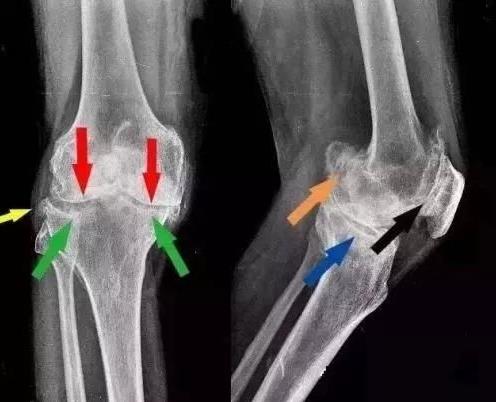

骨折和外伤也是成骨发生的重要诱因,两者都可导致创伤性关节炎,尤其是骨折复位不全,容易造成关节软骨表面不平,从而发生成骨。因此,一旦出现上述问题,就要及时就医,及时诊断和治疗创伤性关节炎,避免关节发生骨质发生。另外,对于骨质增生的患者,要及时就医,防止病情恶化。